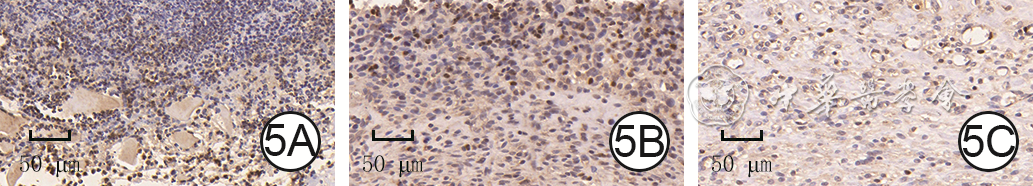

Objective  To explore the effects and mechanism of electroacupuncture stimulation on the survival of multi-territory perforator flaps in rats.  Methods  This study was an experimental study. Thirty male Sprague-Dawley rats aged 8-10 weeks were collected and divided into electroacupuncture stimulation group and control group according to the random number table method, with 15 rats in each group. Doppler blood flow detectors were used to explore the positions of the dorsal deep circumflex artery, posterior intercostal artery, and thoracodorsal artery in the two groups of rats, and a multi-territory perforator flap was designed and resected with the dorsal deep circumflex artery as the pedicle after ligation of the posterior intercostal artery and thoracodorsal artery, and the flap was replanted in situ. Before the operation, the skin in the area containing choke vessels at the junction between the angiosomes of the thoracodorsal artery and posterior intercostal artery (i.e. the choke zone Ⅱ) in the flaps of rats in electroacupuncture stimulation group was subjected to electroacupuncture stimulation for 1 hour per day for 7 consecutive days, while the flaps of rats in control group received no electroacupuncture stimulation. Seven days after the operation, the survival status of the flaps of all rats in the two groups was observed and the flap survival rate was calculated; the skin tissue from the choke zone Ⅱ was collected and stained with hematoxylin-eosin to observe the microvascular neogenesis and calculate the microvessel density (with sample number of 3). Immunohistochemical staining was performed to observe the expression and distribution of vascular endothelial growth factor (VEGF), and Western blotting was used to detect the protein expression of VEGF (with sample number of 3).  Results  Seven days after the operation, the flaps of rats in control group were partially blackened and necrotic, while those in electroacupuncture stimulation group survived with almost no necrosis. The flap survival rate of rats in electroacupuncture stimulation group was (92.1±2.1)%, which was significantly higher than (85.2±1.2)% in control group (t=-10.95, P<0.05). Seven days after the operation, compared with those in control group, the number of new microvessels in the skin tissue in the choke zone Ⅱ of the flaps in rats of electroacupuncture stimulation group increased significantly. The microvessel density in the skin tissue in the choke zone Ⅱ of the flaps in rats of electroacupuncture stimulation group was (21.4±3.0) vessels/mm², which was significantly higher than (11.5±3.7) vessels/mm² in control group (t=-7.34, P<0.05). Seven days after the operation, compared with those in control group, the expression of VEGF in the vascular area of the skin tissue in the choke zone Ⅱ of the flaps in rats of electroacupuncture stimulation group was significantly increased, and the protein expression of VEGF was significantly increased (t=12.56, P<0.05).  Conclusions  Electroacupuncture stimulation can increase the expression of VEGF in choke zone Ⅱ of the multi-territory perforator flaps in rats, improve the blood supply at the distal end of flaps through promoting morphological changes of blood vessels in this zone, thus increasing the survival rates of flaps.

Effects and mechanism of retinoic acid on radiation-induced skin injury in mice

Tian Kai, Yi Yuling, Xu Wushuang, Jia Zou, Wu Pingfan, Sheng Lei, Sun Wei, Zhou Xiaozhong, Wu Lijun

2025, 41(8): 783-792. doi: 10.3760/cma.j.cn501225-20240420-00145

Abstract:

Objective  To investigate the effects and mechanism of retinoic acid on radiation-induced skin injury (RSI) in mice.  Methods  This study was an experimental research. HaCaT cells were obtained and divided into control group (routinely cultured), injury group, treatment group, and antagonism group. The cells in the latter three groups were all exposed to 10 Gy X-ray radiation. The cells in the latter two groups were pretreated with retinoic acid for 12 h before radiation, and the cells in the last group were pre-treated with polyinosinic-polycytidylic acid for 1 h before radiation. Cells from the three irradiated groups at 24 h after radiation and cells from control group at the corresponding time point were collected to detect the reactive oxygen species (ROS) level in the cells by flow cytometry, and measure the protein expressions of interleukin-6 (IL-6), tumor necrosis factor-α (TNF-α), Toll-like receptor 3 (TLR3), and nuclear factor-κB (NF-κB) in the cells by Western blotting, with the sample number being 3. Twenty-four 6-week-old female BALB/c mice were obtained and divided into control group, injury group, treatment group, and antagonism group according to the random number table method (with 6 mice in each group). The right lower limbs of mice in the latter three groups were all exposed to 35 Gy electron beam radiation to induce RSI. Mice in the latter two groups were treated with retinoic acid at 0 (immediately), 7, 14, 21, 28, 35, and 42 days after injury, while mice in the last group were pre-treated with polyinosinic-polycytidylic acid at these time points. Mice in control group were simulated with sham injury. At 42 days after injury, the wound healing rate was calculated, and blood perfusion (denoted as blood flow index) in the skin tissue at the injury site (i.e. wound tissue) was detected by laser speckle flowmetry; wound tissue was collected, the hematoxylin-eosin staining was performed to count inflammatory cells and measure epidermal thickness, the immunohistochemical staining was performed to detect the expression of IL-6 and TNF-α, the immunofluorescence staining was performed to detect the expression of TLR3, and Western blotting was performed to detect the protein expressions of TLR3 and NF-κB.  Results  At 24 h after radiation, the ROS level and protein expressions of IL-6, TNF-α, TLR3, and NF-κB of cells in injury group were significantly higher than those in control group at the corresponding time point (P<0.05). The ROS level and protein expressions of IL-6, TLR3, and NF-κB of cells in treatment group were significantly lower than those in both injury group and antagonism group at 24 hours after radiation (P<0.05). At 42 days after injury, the wound healing rates of mice in control group, injury group, treatment group, and antagonism group were (100.4±2.7)%, (77.5±2.5)%, (89.8±3.2)%, and (70.1±4.8)%, respectively. The wound healing rate of mice in treatment group was significantly higher than that in injury group and antagonism group (both P values <0.05). At 42 days after injury, the blood flow index in the wound tissue of mice in treatment group was significantly lower than that in injury group and antagonism group (both P values <0.05). At 42 days after injury, compared with those in control group, the number of inflammatory cells in the wound tissue of mice in injury group was significantly increased, and the epidermal thickness significantly thickened (P<0.05); compared with those in treatment group, the number of inflammatory cells in the wound tissue of mice in injury group and antagonism group was significantly increased, and the epidermal thickness significantly thickened (P<0.05). At 42 days after injury, the expression levels of IL-6, TNF-α, and TLR3, as well as the protein expressions of TLR3 and NF-κB in the wound tissue of mice in injury group were significantly higher than those in control group (P<0.05), while the expression levels of IL-6, TNF-α, and TLR3, as well as the protein expressions of TLR3 and NF-κB in the wound tissue of mice in treatment group were significantly lower than those in injury group and antagonism group (P<0.05).  Conclusions  Retinoic acid significantly reduces radiation-induced cell injury and promotes the repair of RSI in mice by inhibiting the TLR3/NF-κB signaling pathway and the expression of downstream inflammatory factors.